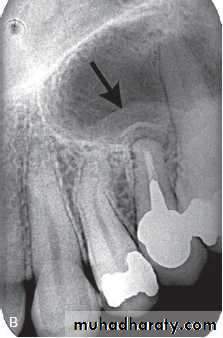

Osteoradionecrosis of the maxilla. (A) before radiotherapy and (B) within 6 months of receiving the radiation. Note the combination of bone sclerosis, bone destruction around the teeth and alveolar crest and widening of the periodontal membrane space.

B

A

Radiographic features: There are no specific radiographic findings with clinically exposed bone.

• Presence of sequestra . • Increase in bone sclerosis. • Widening of PDL space • Thicknening of lamina dura.

( A and B ) of the same patient taken 7 years apart reveal thickening of the lamina dura around the teeth.

( A and B ) of the same patient taken 1 year apart demonstrate a developing sclerotic bone pattern with a sequestra (arrow) related to bisphosphonate therapy.